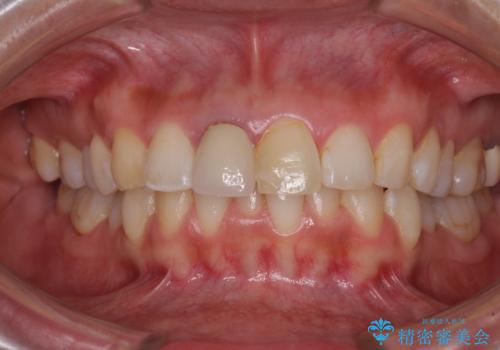

目立つ前歯の詰め物 オーダーメイドのセラミッククラウンで審美的に仕上げる

- 前歯のプラスチックが変色していることを気にして来院された患者様です。

反対側同名歯にセラミッククラウンが装着されていたため、そちらのクラウンと形態や色彩を揃えるようオーダーメイドタイプのオールセラミッククラウンにて補綴することとしました。

2本同時に処置をし、2本とも明るい色合いにすることをお勧めしましたが、今回は1歯のみとしました。

左右のバランスが取れ、患者様には大変満足していただきました。